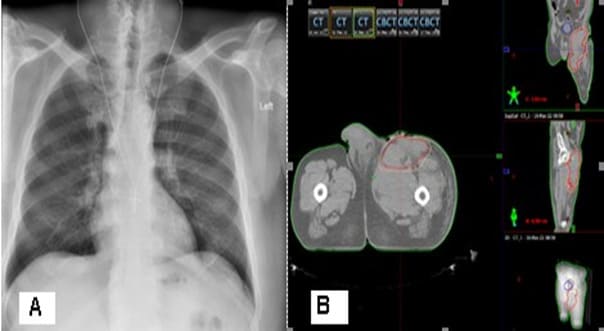

After the second surgery, the patient is not referred for postoperative radiotherapy (RT). Due to the expansion of a painful flushed bump in the upper pole of the operative cicatrix, covering the entire upper half of the thigh with the lisa of plastic and purulent secretions, in May a new operation was performed to maximize the evacuation of necrotic tumor masses and the purulent collection, which passes a submuscular and subfascicular, reaching a vascular nerve bundle. The patient is directed for postoperative RT, which we have considered that due to pain syndrome and available bleeding, should be performed in a palliative aspect. The radiography of the lung is without pathological changes.The pelvic and left lower limb CT reports a large soft tumor, relatively well restricted by the muscles with infiltration of the left inguinal region and the inner part of the left thigh (Figure 8). A decompressive hemostatic Intensity Modulated RT (IMRT) with the technique VMAT up to total dose 20 Gy with daily dose 4 Gy/5 fractions was carried out (Figure 9).

Resectability is strongly related to outcomes, and survival depends upon wide resection [36,37]. Some literature would suggest that patients with localized soft tissue sarcomas may benefit from undergoing re-resection if there was an apparent macroscopic tumor left in the tumor bed. This approach decreases local tumor burden in anticipation of or following local RT [38,39]. In a clinical case presented after the first surgery, no postoperative RT was performed, which is why the tumor continues to persist and aggressively infiltrate adjacent muscle groups. Given the infiltrative nature of the malignant perineurioma and the major difficulties to perform radical surgery with clean resection lines, postoperative RT is required and recommended. The literature generally suggests that RT is most useful in patients with large (e.g., >5 cm), high-grade tumors, and/or those with positive margins at resection [40-42]. In a clinical case presented, a decompressive hemostatic IMRT with the technique VMAT up to total dose 20 Gy with daily dose 4 Gy/5 fractions was carried out (Figure 9). After two weeks of the RT completion, the patient reported a decrease in swelling and pain syndrome, as well as to improve the movement of the limb.